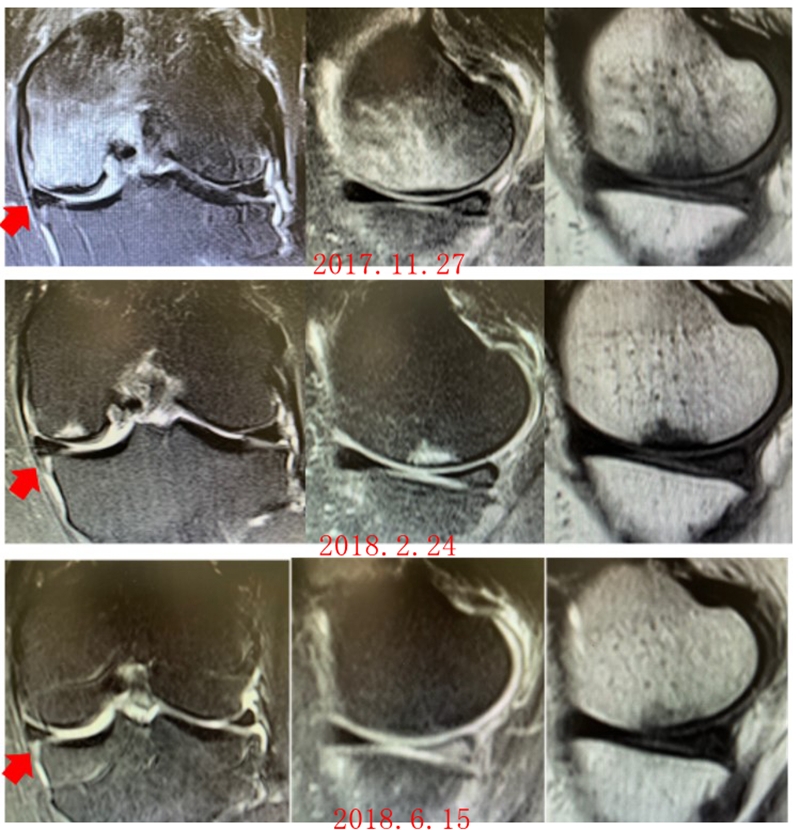

病例:女,65岁,主诉左膝关节内侧疼痛2月余。2017年11月X光未见左膝骨质异常。MR见股骨内侧髁骨坏死,半月板相对突出百分比(RPE)28.3%,合并内侧半月板后根部撕裂,矢状位病变区域前后径为11.67mm,关节线会聚角2.68°

予消炎止痛药物口服、静滴唑来膦酸钠注射液,避免负重6周,后改部分负重,12周后全负重。

2018年2月复查MR见骨髓水肿明显吸收,坏死灶边界清晰,半月板相对突出百分比(RPE)28.92%

2018年6月复查MR见骨髓水肿基本完全吸收,坏死区修复良好,半月板相对突出百分比(RPE)38.54%,患者临床症状消失。

提示坏死好转了,但半月板突出进展了,膝关节的退变加重了。